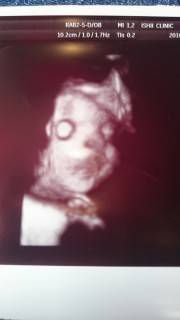

1803gの男の子! 目がなんだかホラーみたい。 頬がぷっくりしててかわいいな~(*^^*) でもすでに二重あご!?